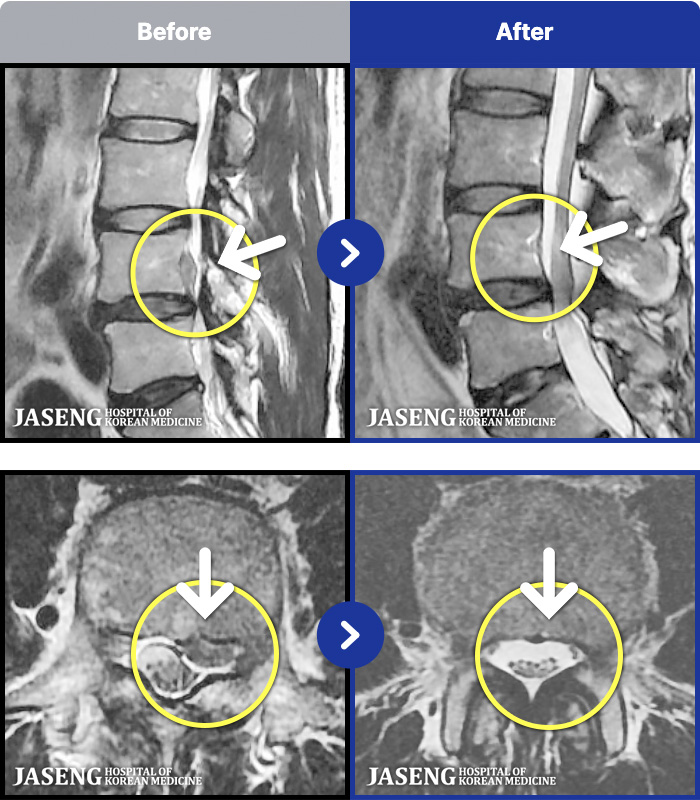

54 MRI ũ ʸ Ȯϼ.